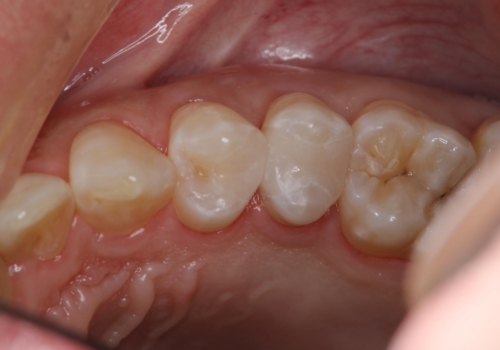

[ オールセラミッククラウン ] すき間の目立つ前歯をきれいにしたい!

担当医 大元洋佑

![[ オールセラミッククラウン ] すき間の目立つ前歯をきれいにしたい!の症例 治療後](https://seimitsushinbi.jp/wp/wp-content/uploads/2024/04/bb98831568fd63b5e5898f71c37cebdf-500x350.jpg?v=1711938371)